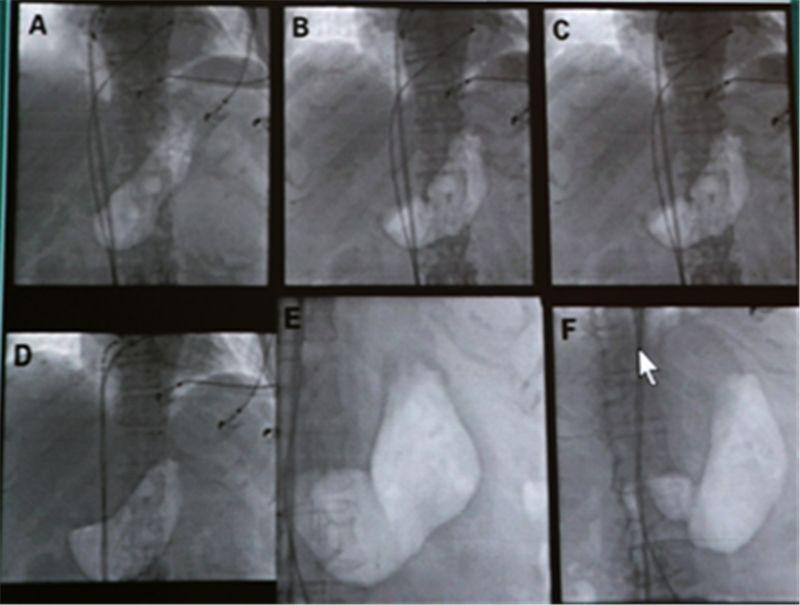

4、手術(shù)治療及新技術(shù):對(duì)于嚴(yán)重病例,手術(shù)可能是必要的,最新的手術(shù)技術(shù)如內(nèi)鏡引導(dǎo)下胃造瘺等,可以在不切除胃腸道的情況下幫助患者緩解癥狀,干細(xì)胞治療和生物反饋治療等新技術(shù)正處于臨床試驗(yàn)階段,有望為胃癱患者提供更多的治療選擇。